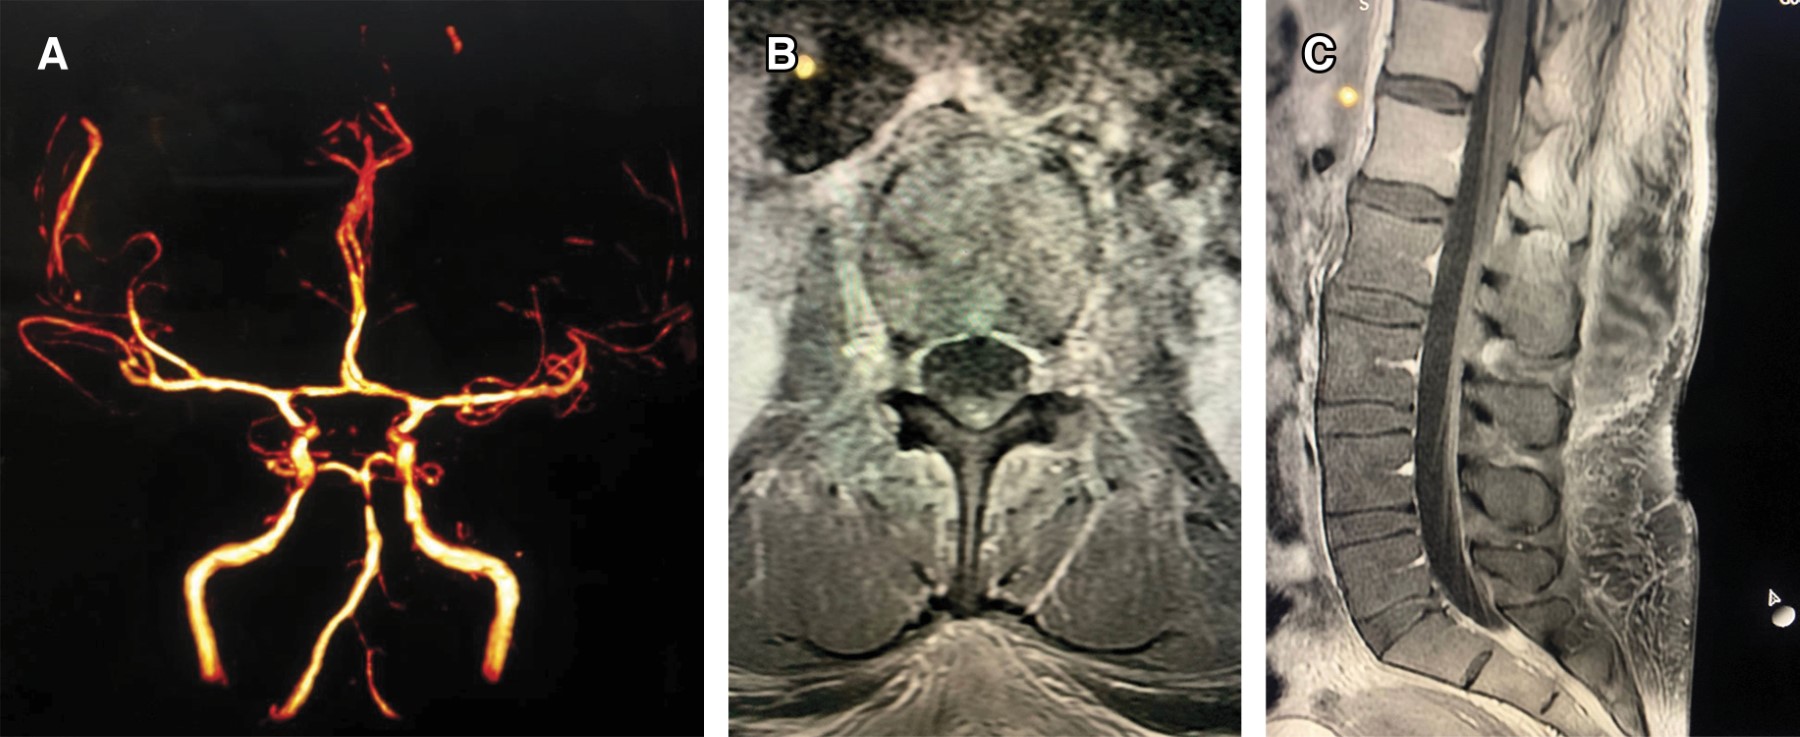

Mujer de 37 años, se le realizó una cesárea bajo anestesia epidural en agosto de 2022, en septiembre inició con cefalea holocraneal de instauración súbita que fue incrementando en intensidad, acompañándose a la semana de rigidez cervical y de espalda. Acudió a varios médicos y recibió manejo sintomático. A la tercera semana se agregó fiebre continua, así como fotofobia, fonofobia y vértigo. Ante la alerta epidemiológica emitida, decidió acudir a un servicio de urgencias, donde se sometió a los estudios estipulados ante la alerta sanitaria. Se toma muestra de líquido cefalorraquídeo con los siguientes resultados: 175 leucocitos, glucosa 35 mg, proteínas 85 mg, por lo que se decide su hospitalización con el diagnóstico de meningitis aséptica probablemente fúngica y se inició esquema antimicótico a base de anfotericina B calculada a 5 mg/kg y voriconazol 300 mg. A los 21 días de haber iniciado su padecimiento presentó de manera súbita disartria, parálisis incompleta de tercer nervio del cráneo derecho, así como dismetría y disdiadococinesia de la extremidad superior izquierda (Síndrome de Claude). La imagen por resonancia magnética mostró un infarto en la unión mesencéfalo-pontina derecha (Figura 1). Durante su estudio se tomó una PCR para Fusarium spp. en el líquido cefalorraquídeo, la cual resultó positiva. Por este motivo la paciente fue enviada a una unidad de cuidados intensivos para vigilancia estrecha y se aumentó la dosis de anfotericina B. La paciente fue sometida a tres punciones lumbares seriadas, completando 14 semanas de tratamiento. Fue egresada con ptosis parcial del ojo izquierdo como secuela.

Figura 1